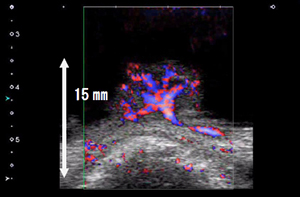

SMIを用いた診断画像

悪性リンパ腫(カラー表示モード) |